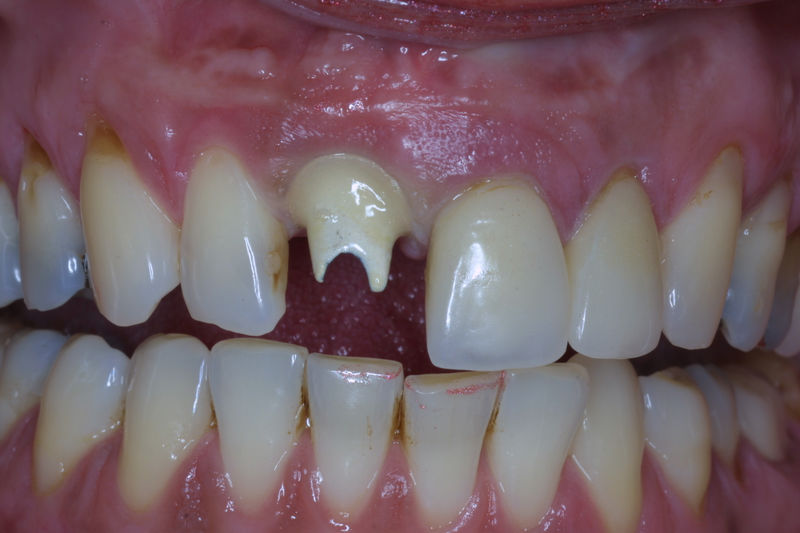

Restauraciones fabricadas en el laboratorio con materiales estéticos, los cuales cubren de manera total dientes anteriores y posteriores. Se utilizan primariamente para restaurar dientes con caries, fracturas y/o defectos amplios, así como soportes de puentes. Para poder enviar el caso al laboratorio se toman impresiones utilizando materiales de impresión o técnicas modernas digitales.

Implante fracasado, extracción, carillas, coronas y prótesis fija.